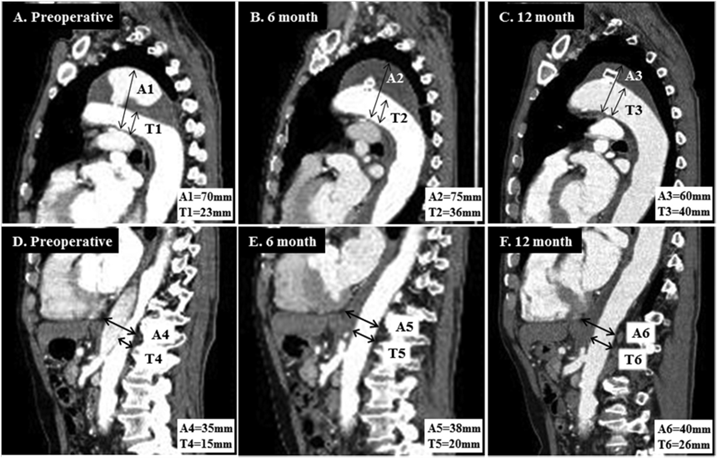

2007~2016年间的14例扩张性慢性主动脉夹层患者(被认为不适合标准治疗)接受了位于主动脉弓(n=6)或降主动脉(n=8)近端破口的腔内血管塞栓塞治疗。其中10例(71%)患者实现了近端破口的栓塞。并在所有10例成功栓塞的患者中,观察到胸主动脉最大直径减小。扩张性慢性主动脉夹层近端夹层破口的腔内栓塞可诱导良好的主动脉重构。对于不适合开放修复或TEVAR的扩张性慢性主动脉夹层患者,采用腔内血管塞栓塞近端破口是一种微创和安全的选择。

病例1为72岁的男子曾因AAA接受治疗,被诊断为70 mm的Ⅲb型主动脉夹层。使用Amplatzer血管塞封闭了5 mm内膜破口,成功修复。患者顺利出院,无并发症,随访CT显示,血管塞无移位,主动脉直径变小。

病例2为75岁女性因Stanford A型主动脉夹层行紧急升主动脉置换手术,残留降主动脉破口。使用AVP Ⅱ顺利栓塞破口,随访影像显示假腔血栓化。

病例3为79岁男性,患者有DeBakey Ⅰ型主动脉夹层。患者不耐受开放手术,使用AVP栓塞近端破口,顺利实现封堵。随访CT显示假腔血栓化。